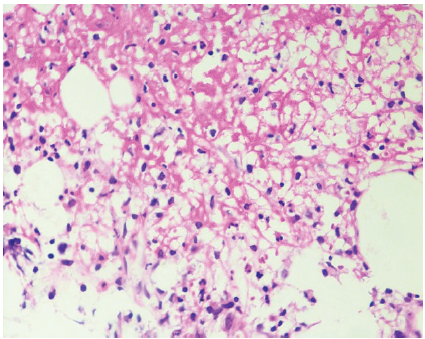

Histopathology revealed necrotizing granulomatous osteomyelitis consistent with a mycobacterial etiology, and Ziehl–Neelsen staining demonstrated occasional acid-fast bacilli (Figs. 5 and 6). Based on these findings, a diagnosis of tubercular osteomyelitis of the pubic symphysis with secondary MRSA infection was established.

Figure 6: Photomicrograph showing necrotic material with epithelioid histiocytes, neutrophils, and plasma cells, consistent with necrotizing granulomatous inflammation (Hematoxylin and Eosin, ×400).